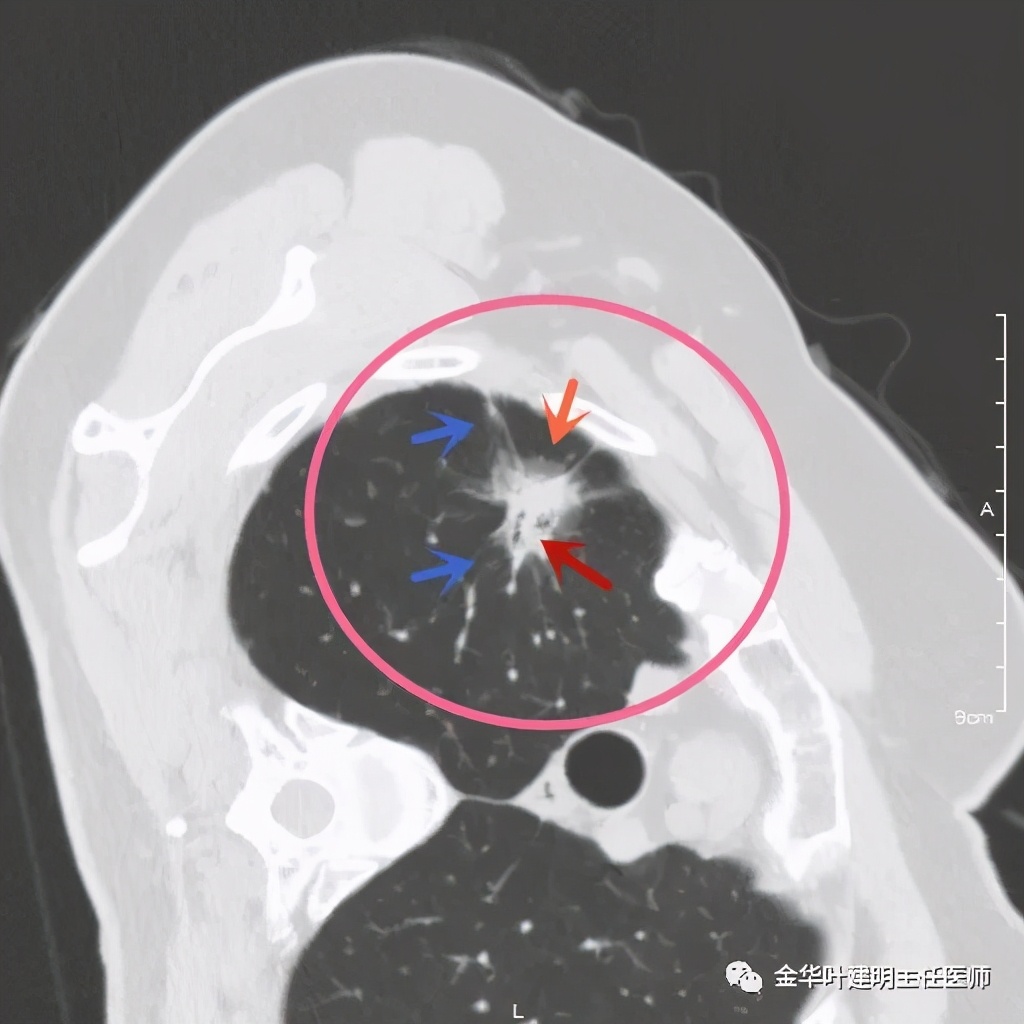

四、浸润性腺癌贴壁伴恶性度较高的实性成分:

影像特征:浸润性腺癌的贴壁生长型若伴有乳头、微乳头、实体型等成份时,更是典型的恶性的特征。此例是贴壁占60%,乳头成分占40%。我们来看其特点:桔色箭头示磨玻璃成分(代表贴壁生长部分),中央是实性成分(代表乳头生长部分),而且实性部分有收缩力(病灶向中间拉的趋势),密度高的部分又其内部密度不大均匀,毛刺也是长短不一。也就是说: 混合磨玻璃结节伴实性部分的收缩力 是其最显著的特点。实性部分若是实体型,也一般是类似表现。预后情况主要看实性成份的占比及亚型,因为贴壁成分是恶性度不高的,但若位微乳头或实体型,那便预后会差一些。也比腺泡型差。